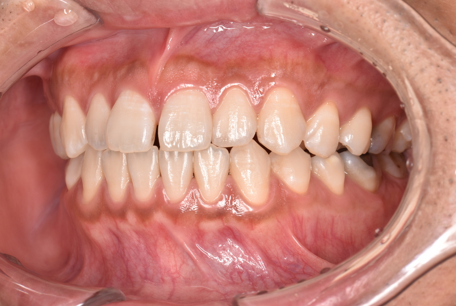

治療後

| 術後の経過・現在の様子 | 予定通りに治療が完了しました。 患者様にも「思っていたより痛みもなく、綺麗に並んで嬉しい」とご満足いただけました。 |